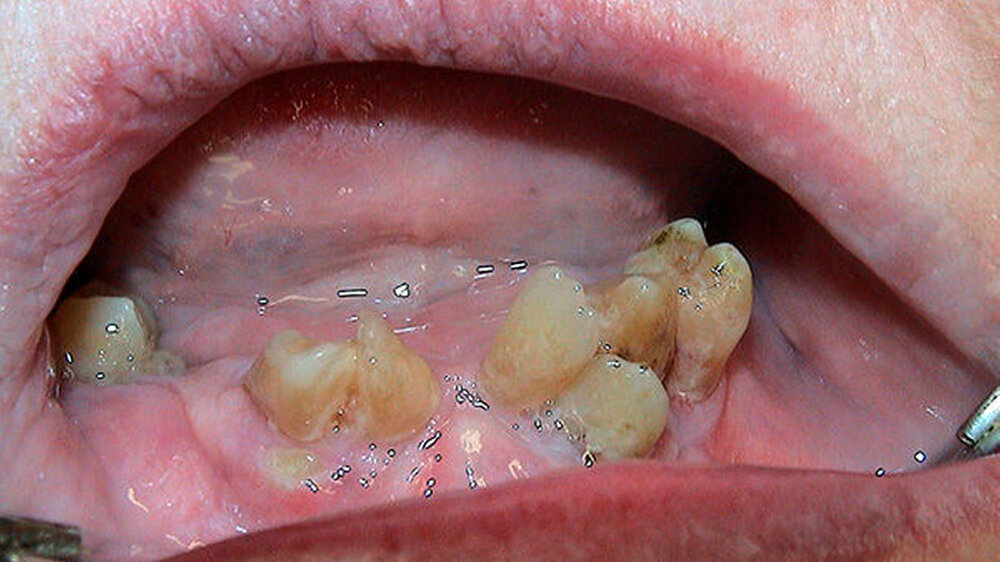

Es ergab sich ein absolut überraschendes und in dieser Form sicherlich einmaliges Bild: Sowohl im Ober- als auch im Unterkiefer befanden sich durchgebrochene, zum Teil gekippte Zähne, die topografisch nur schwer zuzuordnen waren und von dem eingegliederten Zahnersatz vollständig bedeckt wurden (Abbildungen 3 und 4).